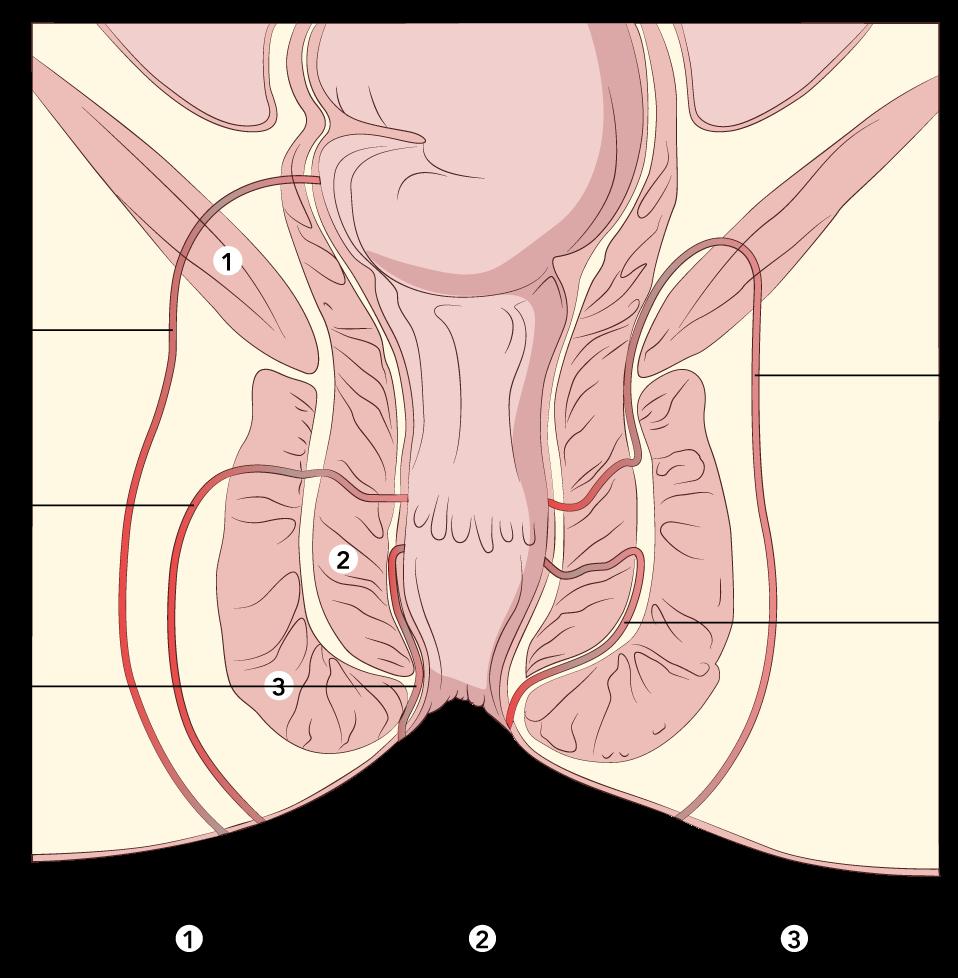

FÍSTULAS ANORRECTALES

Definición Clasificación

Trayecto anormal entre el conducto anorrectal y la piel usualmente por un absceso previo.

Tenemos la clasificación de Parks:

Interesfinteriano (tipo I de Parks) es la más frecuente (ENARM 2002)(ESSALUD 2007,2015)

Curso: a lo largo del espacio anatómico entre el esfínter interno y externo

Apertura: piel perianal y / o recto

Transesfinteriana (tipo II de Parks)

Curso: penetra el músculo esfínter externo del ano hacia la fosa isquiorrectal

Apertura: piel perianal

Supraesfinteriano (tipo III de Parks)

Curso: asciende caudalmente dentro del espacio interesfinteriano, penetra el músculo elevador del ano y sigue caudalmente hacia la fosa isquiorrectal

Extraesfinteriano (tipo IV de Parks)

Curso: desde la apertura interna de la ampolla rectal (por encima de la línea dentada) a través de los músculos elevadores del ano.

Fístula extraesfinteriana

Fístula transesfinteriana

Fístula supraesfinteriana

Fístula interesfinteriana

Figura 56. Tipos de fistulas según la clasificación de Parks